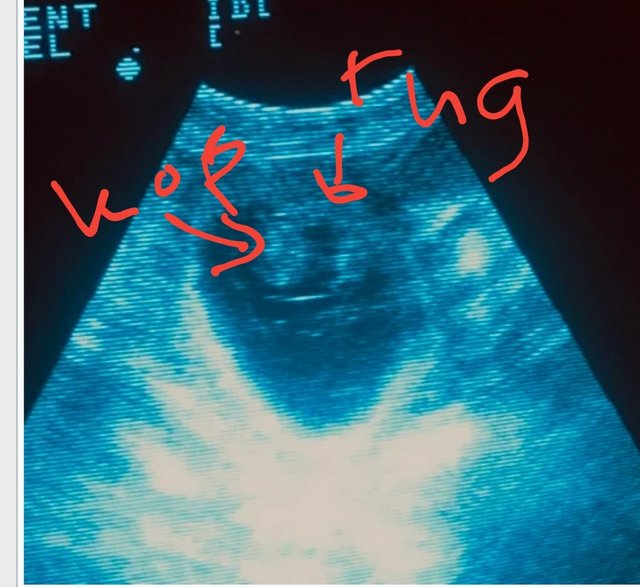

Re: Mira. Echo gehad! pag. 45

Re: Mira. Update echo pag. 45

Proficiat! Zo leuk dit!Cleva schreef:Vandaag was de echo. Nou, ze waren niet moeilijk te vinden. De echo werd op haar buik gezet en ik zag al meteen een hartje kloppen!

Minstens 5 vruchtjes!Waarschijnlijk nog wel een paar meer.

Is die koptelefoon bovenin een pupje? Ben niet zo bedreven in het lezen van echo's. Maar ik heb de foto mooi wel opgeslagen

Haha, nee t lichte deel dus. Mooi om te zien hè! Vooral bewegend dan . Vond ik toen Yara drachtig was ook zo mooi. En dan binnenkort kan je ze voelen bewegenCleva schreef:Oh zo!! Dankjewel!

Ik zat naar het donkere deel te kijken.

Leuk he! Ik vind dat altijd zo leuk om te zien al zie je bijna niets. Dit vind ik ook zo'n aparte foto, ooit van internet geplukt. De baarmoeder met pups.